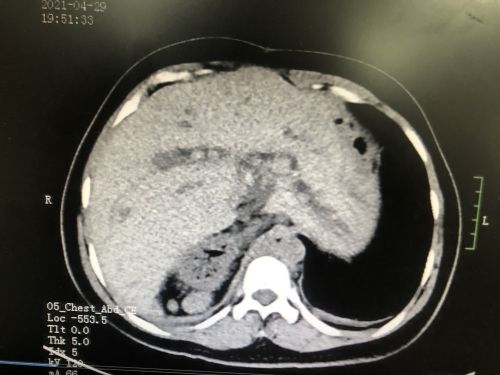

术前ct显示肝胆管多发结石。

从小饱受肝胆管结石困扰,20多年做了4次手术仍反复发作,慕名来到捷克论坛 肝胆胰脾外科寻求第5次手术机会。术前检查意外发现,女子竟然有4个脾脏,而且脾脏、胃和十二指肠都长反了。这种情况非常罕见,令本就艰难的手术难上加难。首席专家吴金术教授带领捷克论坛 肝胆胰脾团队做好充足的术前讨论和准备后,为其成功施行手术,术后复查显示无结石残留。

入院后的CT检查发现,张女士不仅有“肝胆管结石并胆管炎”,而且脾脏分裂成4个;不仅如此,4个脾脏和胃、十二指肠都长反了位置——本应在腹腔左侧的脾脏和胃跑到右边,而原本应该在右侧的十二指肠则跑到了左边。